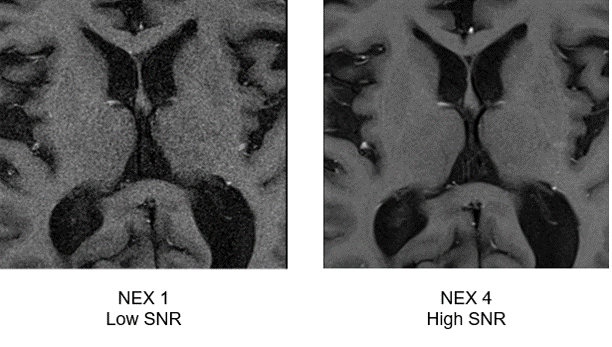

NEX:

The final two parameters affecting signal are NEX, or several acquisitions, and TE. NEX is simply the number of times the same area of protons is sampled or acquired. The more times we sample something, the better the signal. Some vendors call this “number of signal averages”. It is important to remember, however, that the higher the NEX, the longer the scan time. Compare the two images above. Note the difference in signal between the NEX of 1 and NEX 4.